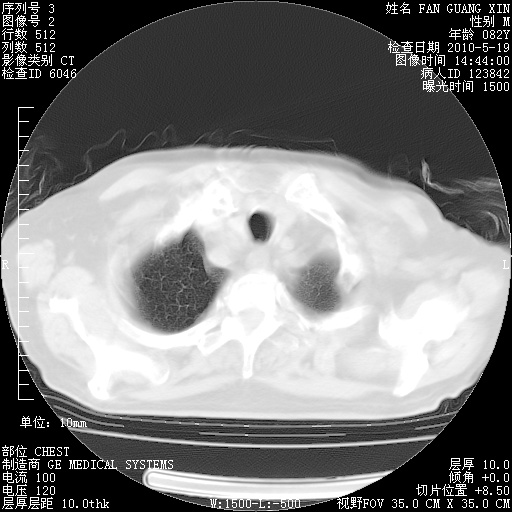

复查肺部CT,明显好转。为什么发热呢?

治疗3周后的肺部CT